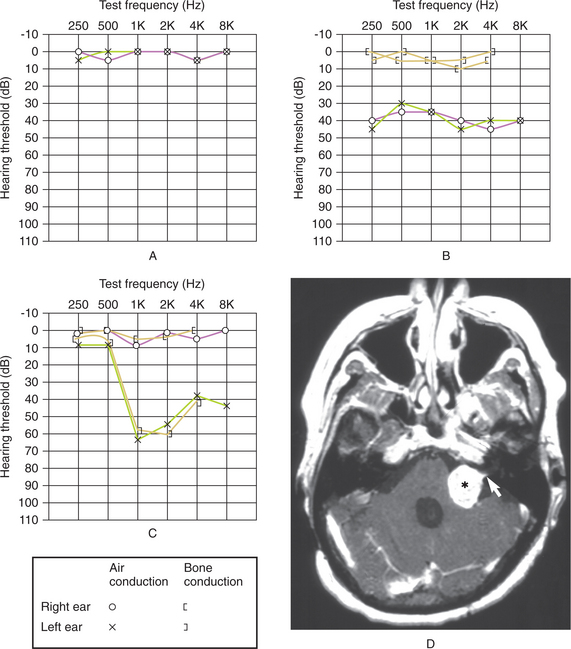

An audiogram, or test of hearing, typically demonstrates low-frequency hearing loss on one side. Perceived hearing loss can be difficult to verify without audiometry, especially during an exacerbation of tinnitus or aural pressure. Improvement in audiograms can reflect better control of fluid, and decreases in hearing are suggestive of progressive disease.63